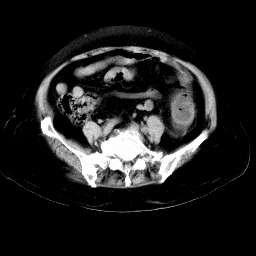

以下是引用余辉在2008-11-9 9:47:00的发言:[br]各层面均可见降结肠管壁增厚,管腔狭窄,中部层面可见管壁明显增厚区,结合病史多考虑降结肠癌,溃疡性结肠炎不除外,建议进一步检查